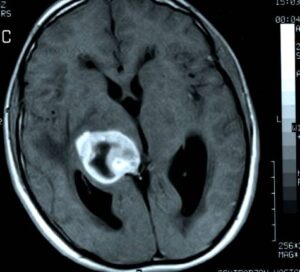

3. Nörogörüntüleme Yöntemleri

Günümüzde Parkinson hastalığında klasik beyin MR’ı genellikle normal çıkar. Ancak fonksiyonel görüntüleme teknikleri erken tanıda yardımcı olabilir: